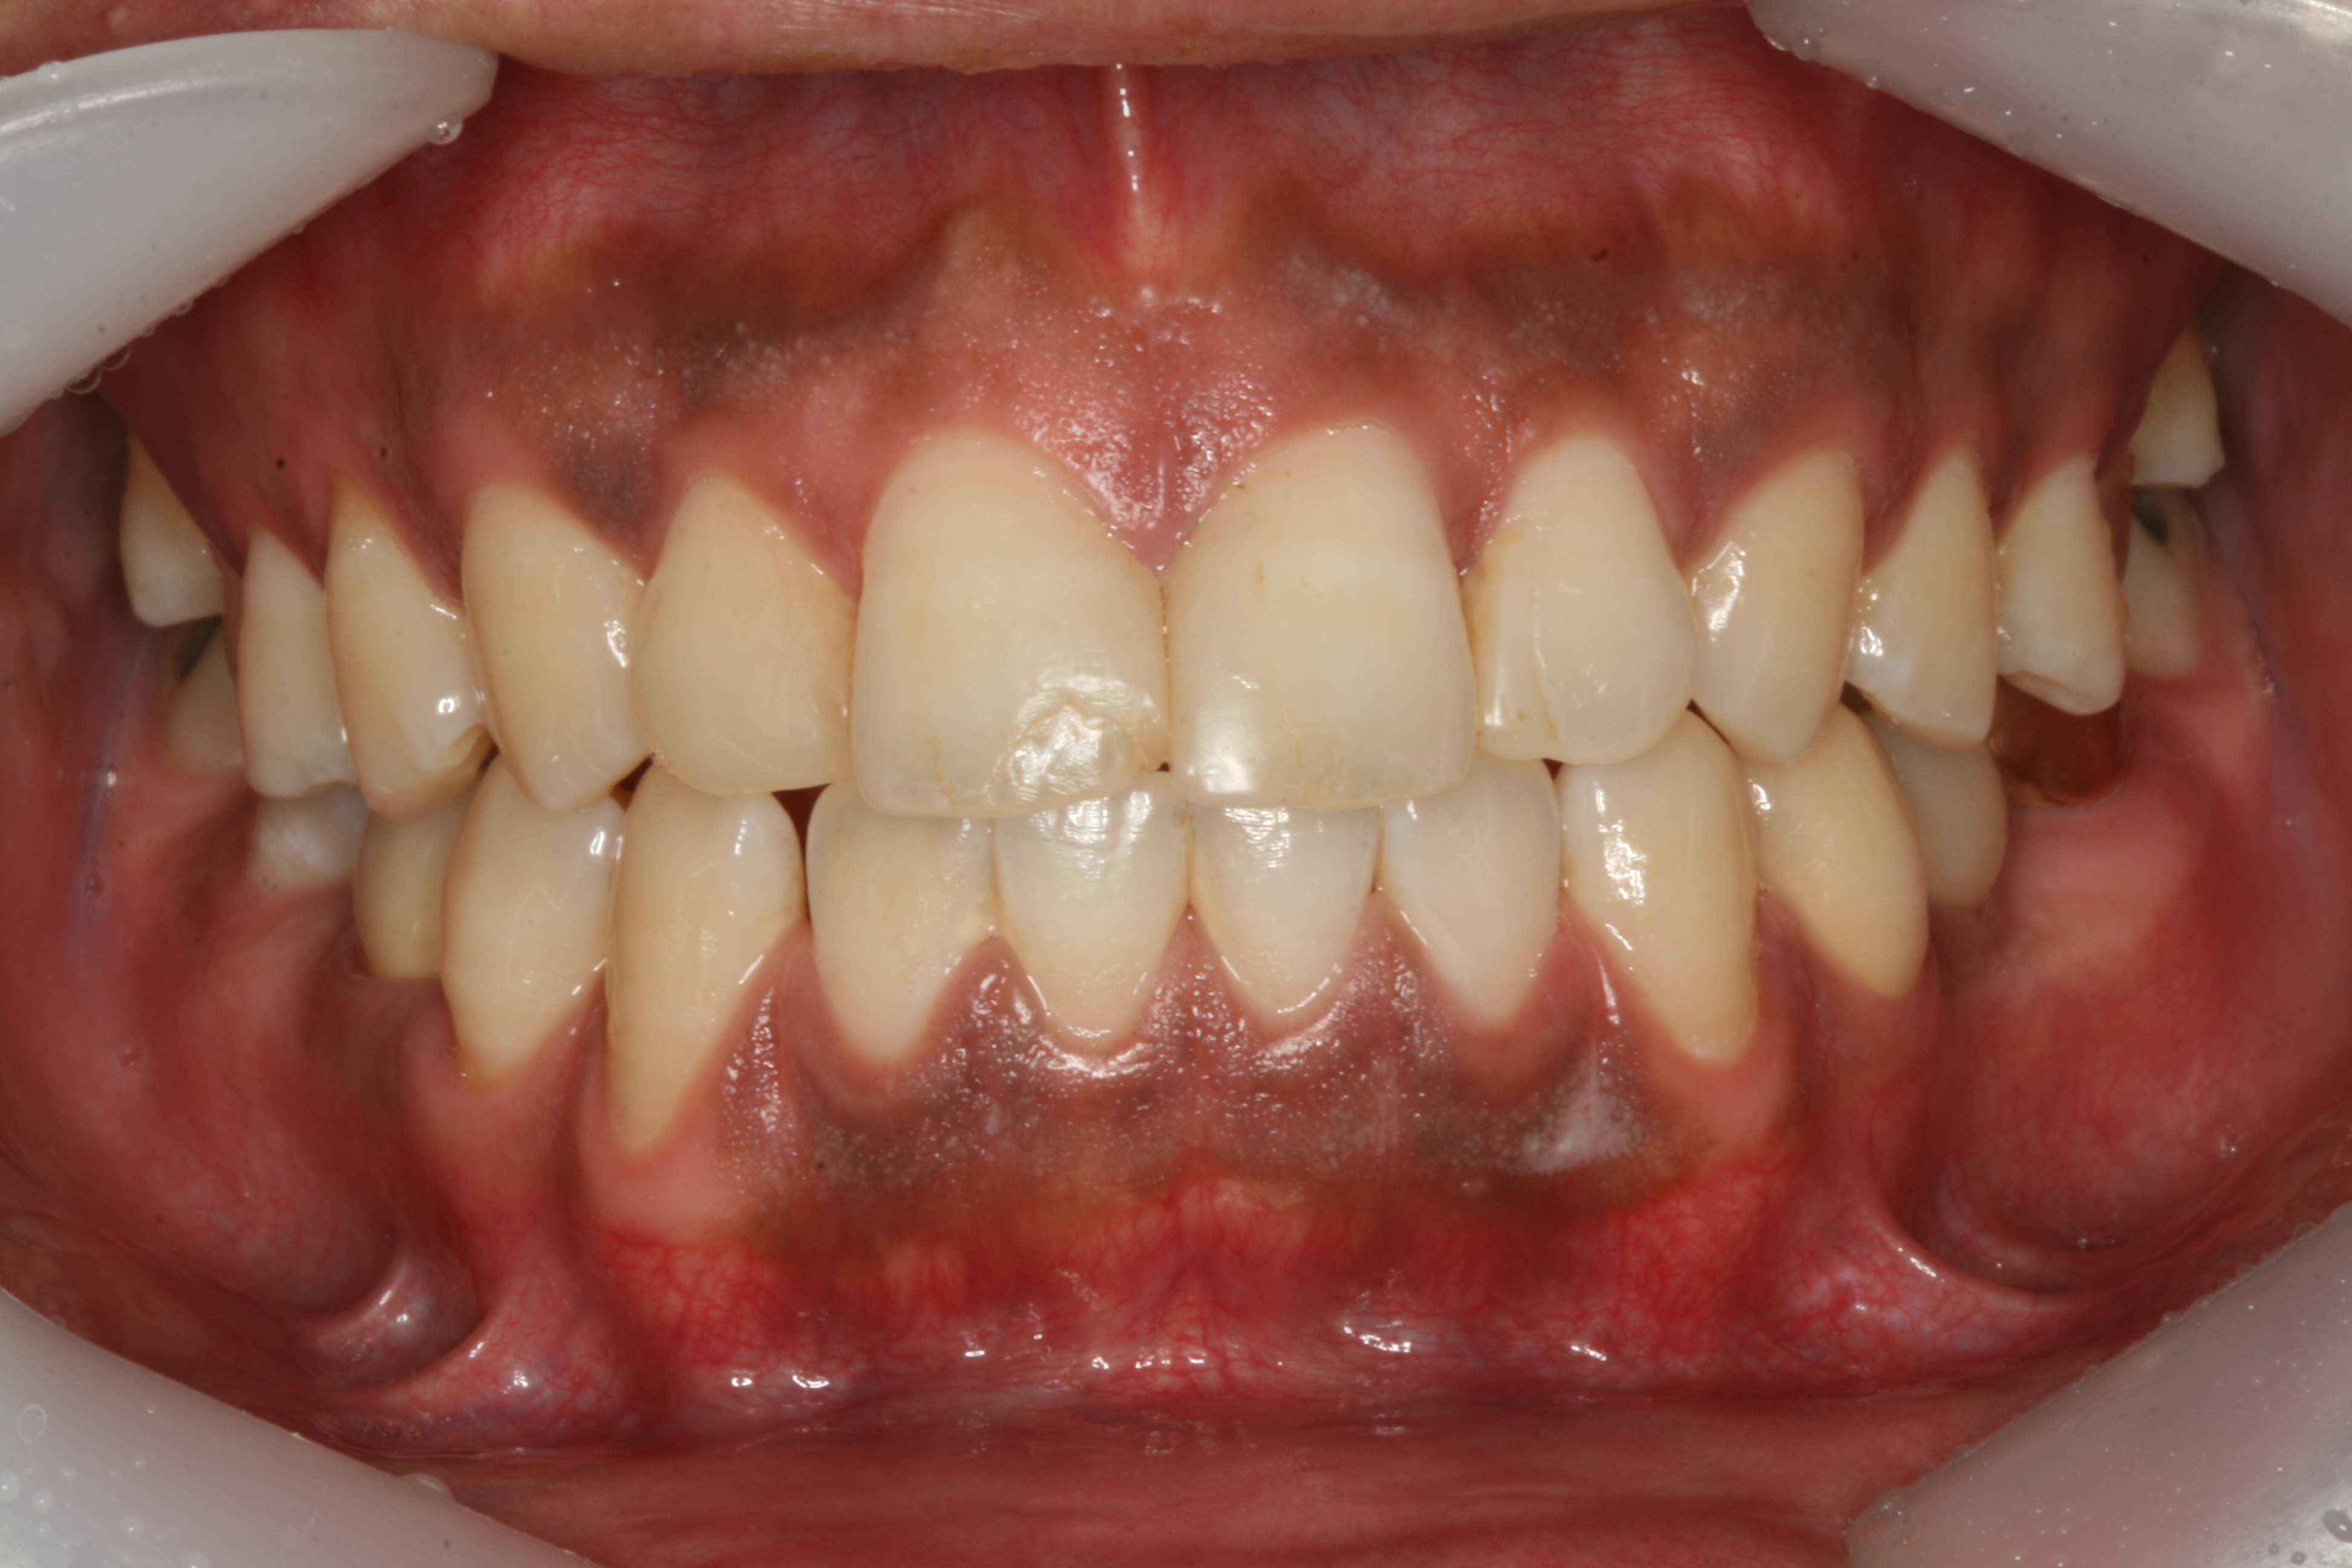

아래 사진은 과도한 멜라닌 색소의 침착으로 검은 잇몸을 보실 수 있습니다